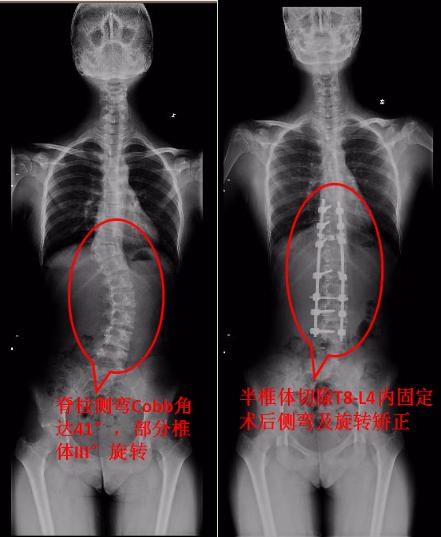

林宏生教授详细了解小小的情况后,并为她进行了精细的检查,确诊为T10半椎体畸形并脊柱侧弯。X线可见患者脊柱发育不良,CT提示半椎体畸形为完全分节,脊柱侧弯Cobb角达41°,部分椎体旋转III°,Risser征 III°。

明确诊断后,林教授制订了详细的手术方案,决定给她施行半椎体切除,椎间植骨,后路T8-L4矫形椎弓根钉棒内固定术,整个手术过程十分顺利,仅4小时便完整切除了半椎体,并彻底矫正了小小的侧弯畸形,去除了椎体旋转。手术后,小小不仅双肩等高、剃刀背消失,身高还比手术前增加了2厘米!